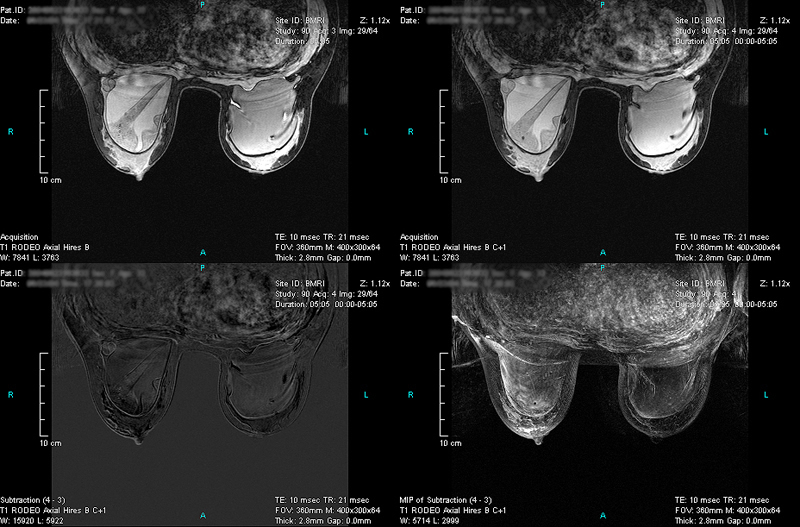

Case 4 - Silicon Implant Ruptured

(from left to right, top to down)

RODEO Pre (unspoiled), 1st Post (spoiled), Subtraction and MIP of Subtraction.